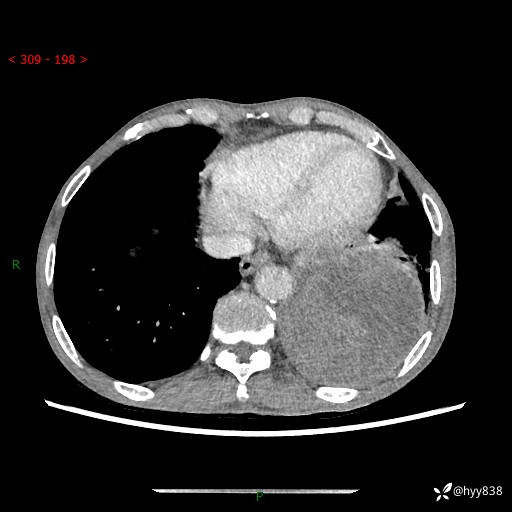

77岁/男,腹痛2月,CT发现左肺占位1天。巨大肿块,肺内或肺外来源…结果公布~

主诉:腹痛2月,CT发现左肺占位1天

现病史:患者于2025年9月间断左下腹胀痛,在当地镇卫生院行彩超检查考虑泌尿系结石,行止痛排石对症治疗未见明显好转;1天前腹痛症状加重,至当地市第三人民医院行CT检查:左肺下叶巨大团块状软组织影,考虑肿瘤性病变,建议增强CT检查;左侧胸腔积液;纵膈内淋巴结肿大;双肺肺气肿;右肺中叶纤维灶。为进一步求治,来我院就诊。

胸部CT平扫+增强